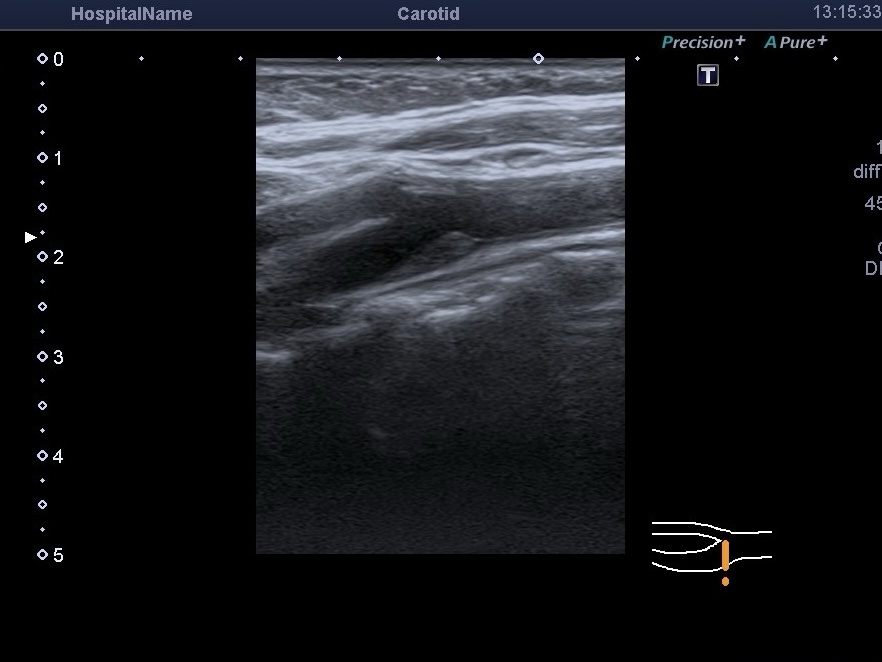

У продовження теми атеросклеротичних бляшок (АСБ), які ми виявляємо під час УЗД судин шиї. Нещодавно з’явилися цікаві дослідження щодо впливу геометрії та форми АСБ на ризик виникнення ішемічного інсульту у пацієнтів з помірним стенозом. Згадане дослідження форми бляшки проводилося лише для внутрішньої сонної артерії (ВСА).

Підбиваючи підсумки: не всі атеросклеротичні бляшки однакові. І навіть їхня форма — це важливий параметр, який допомагає лікарю оцінити, наскільки стабільною є бляшка та наскільки високим є ризик інсульту у пацієнта. Інформація, отримана за допомогою УЗД судин (як В-режим, так і різні види доплерівського режиму), дозволяє обрати правильну тактику лікування для кожного конкретного випадку.

Це можливо лише під час експертного УЗД судин шиї з використанням доплерівських режимів. Лікар бачить потік крові в реальному часі та оцінює його стабільність.